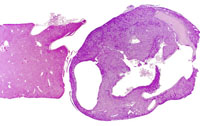

A discrete cholangiocarcinoma protruding above the natural surface of the liver. Higher magnification shows poorly formed glandular structures and a minimal scirrhous reaction.